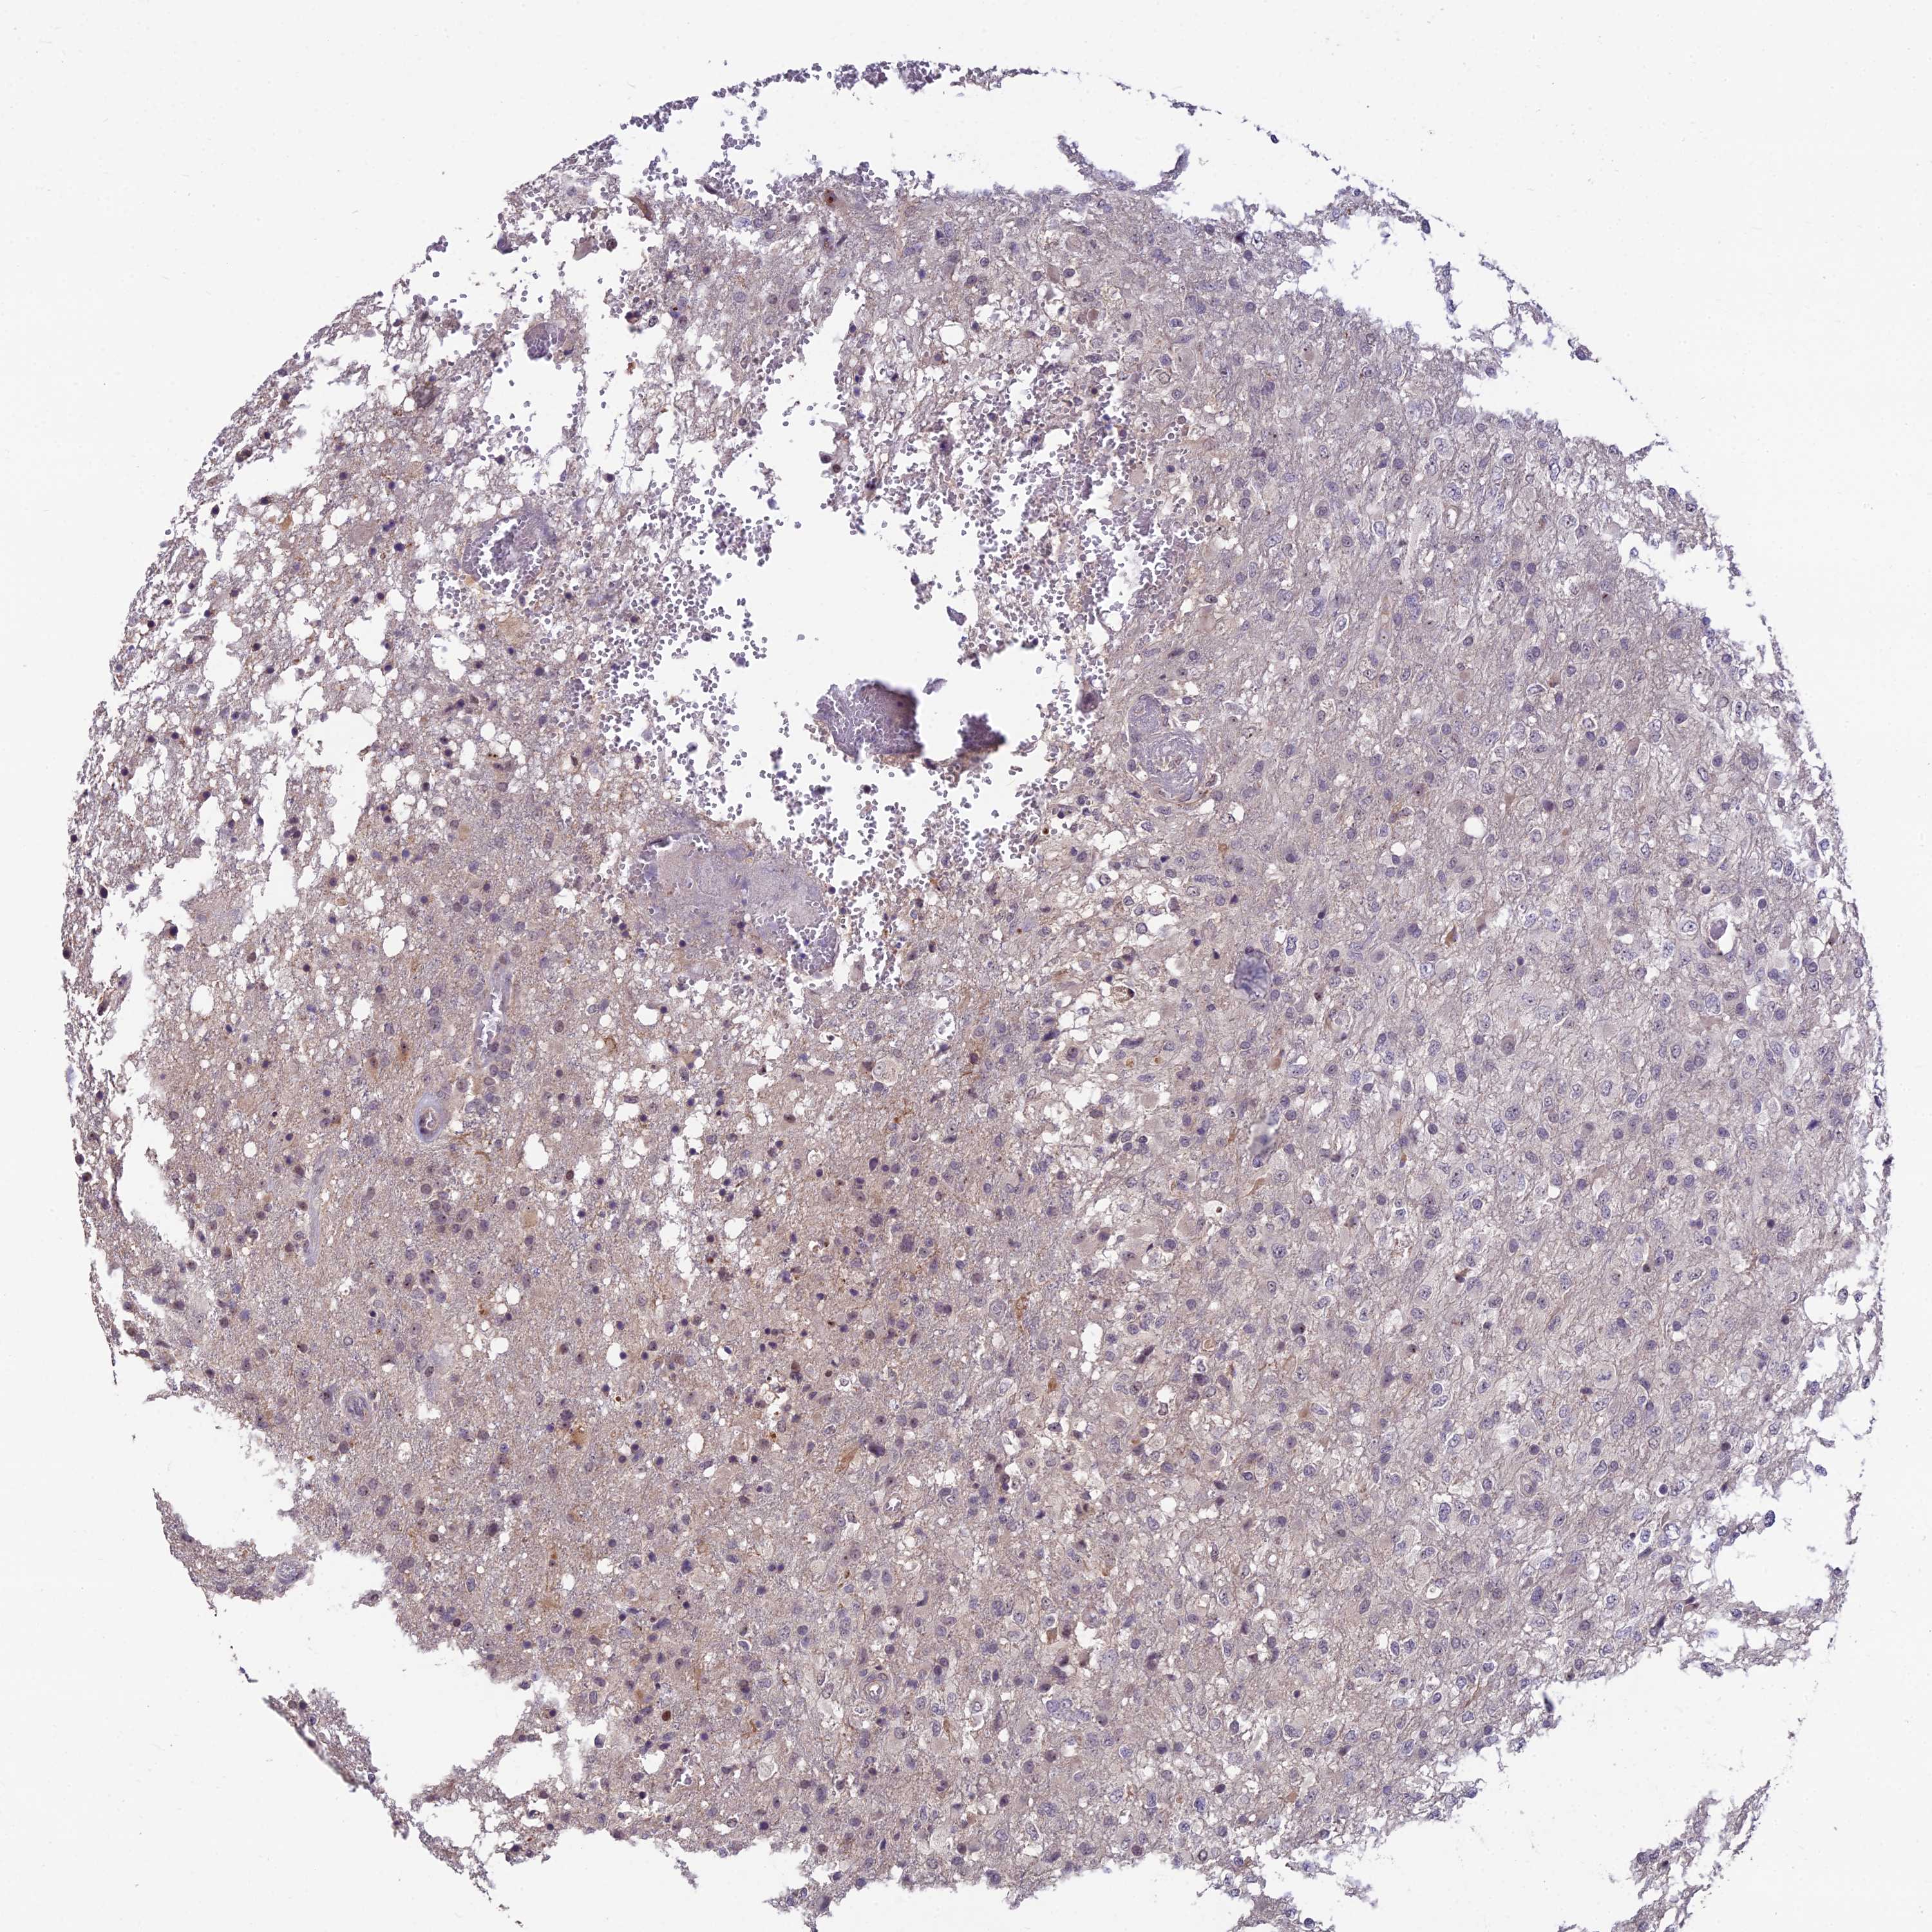

GLIOMA - Protein expressioni

A mouse-over function shows sample information and annotation data. Click on an image to view it in a full screen mode. Samples can be filtered based on level of antibody staining by selecting one or several of the following categories: high, medium, low and not detected. The assay and annotation is described here.

Note that samples used for immunohistochemistry by the Human Protein Atlas do not correspond to samples in the TCGA dataset.

Antibody stainingi

Antibody staining in the annotated cell types in the current human tissue is reported as not detected, low, medium, or high, based on conventional immunohistochemistry profiling in selected tissues. This score is based on the combination of the staining intensity and fraction of stained cells.

Each image is clickable and will lead to virtual microscopy that enables deeper exploration of all samples and also displays staining intensity scores, fraction scores and subcellular localization as well as patient and tissue information for each sample.

Antibody HPA043973

Staining

High

Medium

Low

Not detected

Intensity

Strong

Moderate

Weak

Negative

Quantity

>75%

75%-25%

<25%

None

Location

Nuclear

Cytoplasmic/membranous

Cytoplasmic/membranous,nuclear

Glioma, malignant, High grade

Glioma, malignant, Low grade